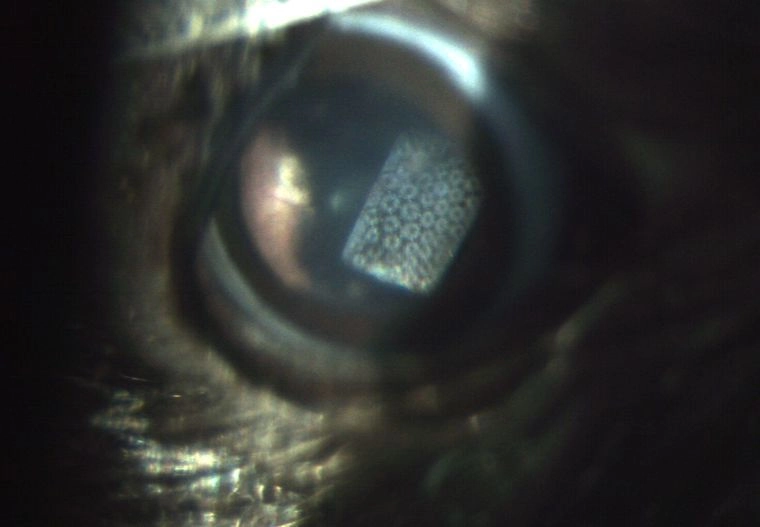

Technology for restoring vision is still at an early stage, but a new kind of retinal prosthesis allows blind rats to sense light, a study shows.

The new device was implanted in the eyes of visually impaired rats. Exposing the prostheses to light elicited a response in the part of the rats' brains involved in visual processing, researchers reported online today (June 18) in the journal Nature Communications. The device offers promise for restoring vision in degenerative diseases of the eye.

Mandel and his colleagues developed a wireless prosthesis that projects camera images onto the retina using near-infrared light (light just outside the spectrum humans can see). A solar cell implanted beneath the retina converts the light into electric current, which activates neurons in the retina. [Images: Eye Implant Restores Vision to Blind]

In the current study, the researchers implanted their retinal prosthesis in rats with degenerated retinas. The team shone light on the prostheses and measured the responses in the vision area of the animals' brains, known as the visual cortex.